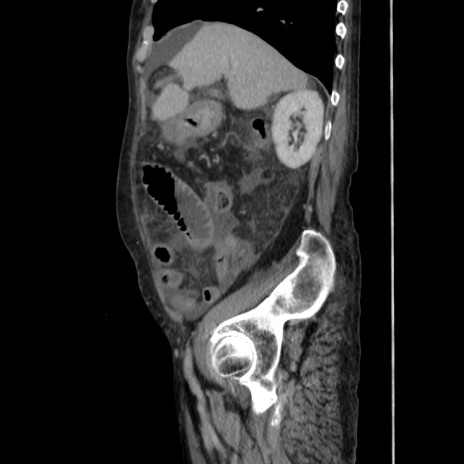

横断像

【症例】80歳代 女性

【主訴】腹部膨満感

【現病歴】他院にて肝硬変にてフォロー中。1週間前から便秘、腹部膨満感、臍部腫瘤あり受診となる。

【既往歴】肝硬変

【身体所見】腹部膨隆あり、皮膚変化なし、疼痛なし。

【データ】WBC 4600、CRP 0.25